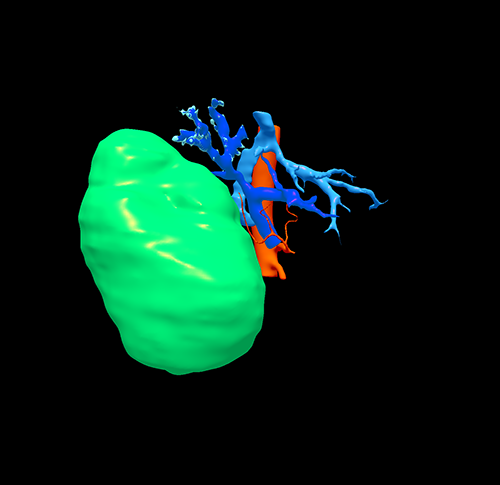

右肝巨大肝癌---右半肝切除